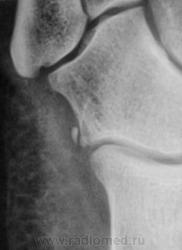

Травма.   Пациент направлен на рентгенографию стопы.

не увеличение, то такой перелом очень легко пропустить.

Os peroneum, сверхкомплектная кубовидная

кость, может являться сесамовидной костью в

сухожилии длинной малоберцовой мышцы.

Os calcaneocuboideum laterale, добавочная

кость, возможно, что это образование

является персистирующим апофизом латерально-

верхнего края пяточной кости или прилежащим

краем кубовидной кости.

Мелкие кости, действательно, не похожи на отломанные фрагменты. Но в кубовидной кости имеется линия, подозрительная на перелом, а кость эта, хоть и редко, но ломается.